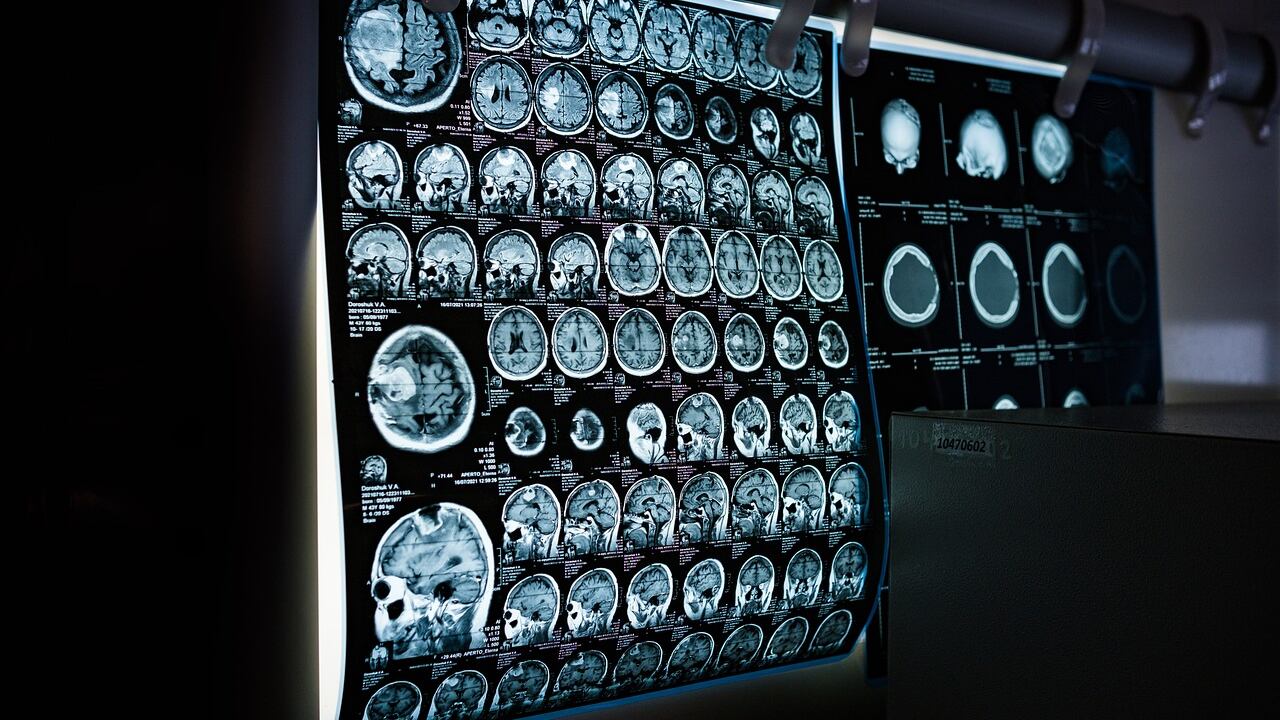

Un informe publicado por la Organización Mundial de la Salud (OMS) reveló que aproximadamente una de cada tres personas en todo el mundo sufre de trastornos neurológicos como migraña, ataques epilépticos y demencia.

Los accidentes cerebrovasculares (ACV, por sus siglas en inglés) es la patología que más causa las mayorías de las discapacidades y problemas de salud.

A los ACV, le continúa en la lista la encefalopatía neonatal, la demencia tipo Alzheimer, las consecuencias neurológicas de la diabetes, la meningitis y la epilepsia. La lista completa de las afecciones neurológicas que contribuyen a la pérdida de salud en el último año fueron:

- Accidentes cerebrovasculares

- Encefalopatía neonatal.

- Migraña.

- Demencia.

- Neuropatía diabética.

- Meningitis.

- Epilepsia.

- Trastornos del espectro autista.

- Cánceres del sistema nervioso.